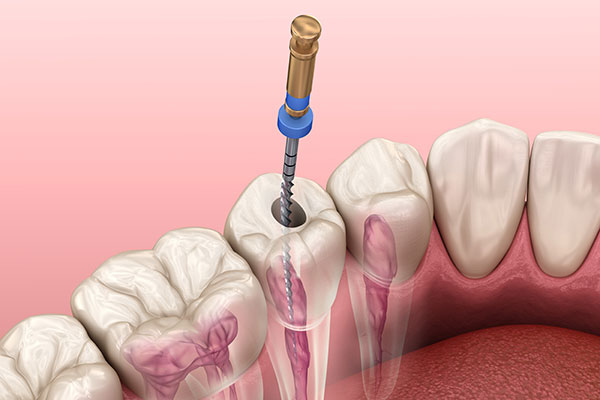

• ニッケルチタンファイルによる精密な処置

ラバーダム防湿は、治療する歯だけをゴム製のシートで隔離し、唾液や細菌の侵入を防ぐ方法です。根管内を無菌的な環境に保つことで、再感染のリスクを大きく低減できます。また、柔軟性に優れたニッケルチタンファイルを使用することで、複雑に湾曲した根管にも追従しやすく、歯を削りすぎることなく、精密で安全な根管形成が可能になります。こうした基本を徹底することが、歯を長く守る治療につながると考えています。